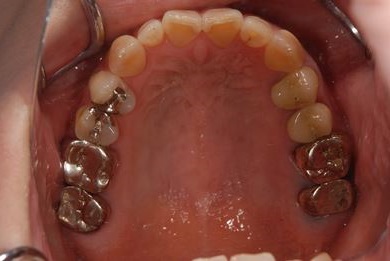

治療前

• 治療前